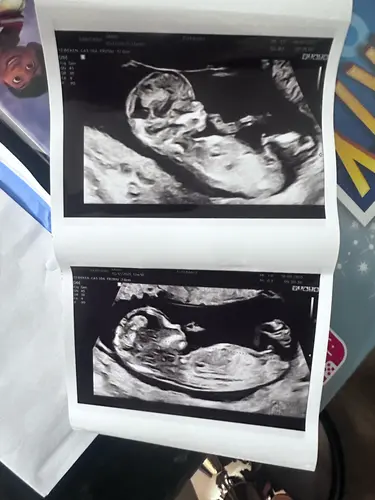

Kan iemand al het geslacht hierop bepalen met de nubt en super benieuwd

Nu ben ik toch ook wel heel nieuwsgierig. Heeft iemand een idee? 🩷💙

Beste NUB tuurders. Wij zijn enorm nieuwsgierig. Wie durft een gok te wagen?